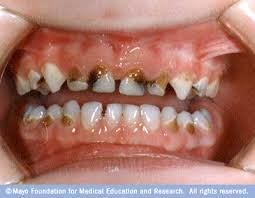

Hermanus-based, Dr Righardt van Huyssteen is a dental practitioner with more than 15 years of dental experienc...